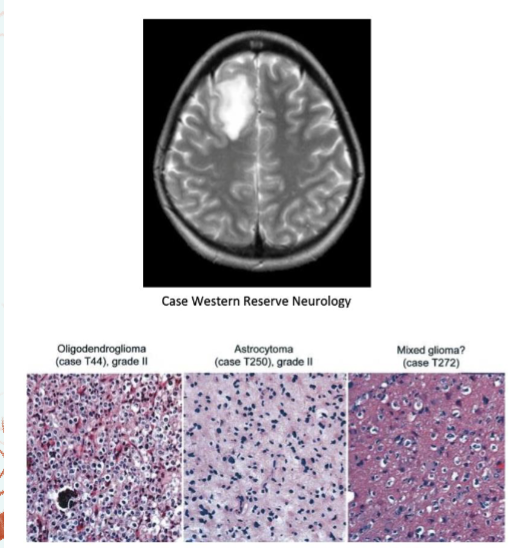

Diseases of the Astrocyte

Astrocytoma- a tumor originating from an astrocyte

Glioblastoma multiforme is the most aggressive form, grade IV

Diseases of the oligodendrocytes

Oligodendrogliomas are tumors that arise from oligodendrocytes

are tumors that arise from oligodendrocytes